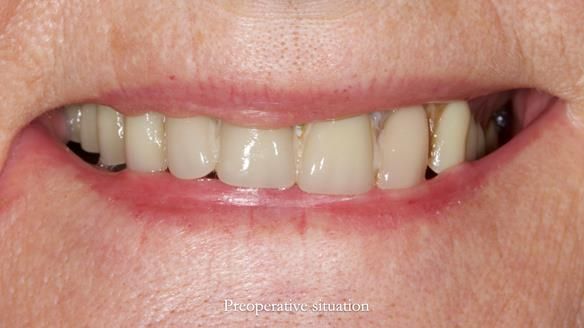

Mary was referred to me by her cousin, who is a dentist. She wanted help with new dentures but made it clear from the start that she didn’t want dental implants. She’d heard about previous implant failures and was already very comfortable wearing dentures. Her neuromuscular control was excellent.

Mary’s upper occlusal plane wasn’t parallel to her interpupillary line, and she specifically wanted that natural asymmetry preserved. Rowan arranged the teeth beautifully, following the exact contour and character of her original smile.

For both the upper and lower dentures, we used Schottlander Enigma Life teeth. I’ve been using these since 2014 and they’ve been outstanding - the surface texture, colour depth, and light reflection are superb. When arranged to mirror the patient’s natural tooth positions, they look completely lifelike.